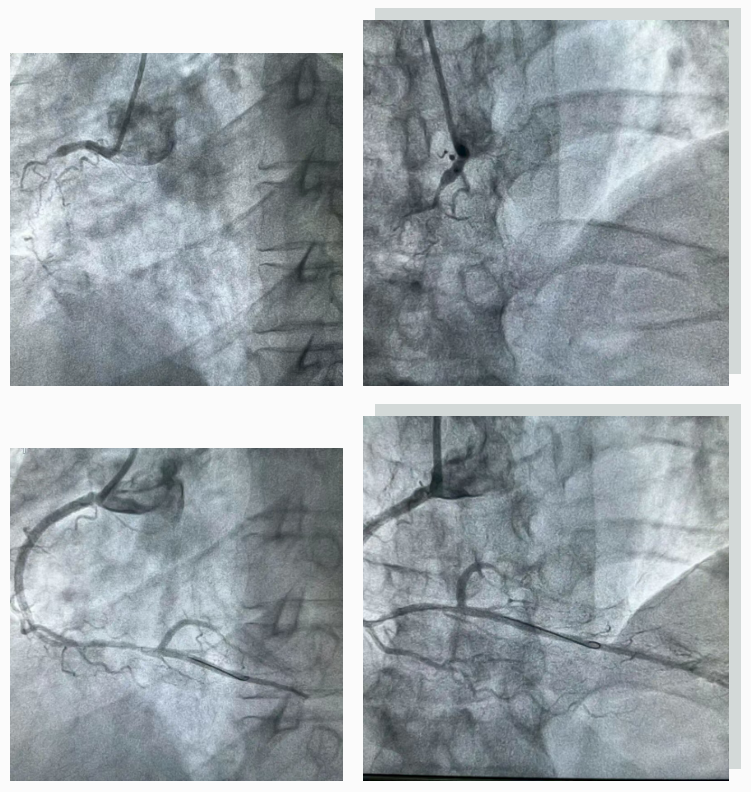

78岁患者王大娘因突发胸痛入院,急诊心电图提示广泛前壁心梗梗死伴低血压。“时间就是心肌,时间就是生命”,面对危急病情,胸痛中心绿色通道迅速响应,杨俊杰与当地医院心内科介入团队马上进入待命状态。患者通过无缝衔接的转运流程到达医院后,杨俊杰再次结合患者检查结果评估病情,果断作出决策:为患者实施急诊冠状动脉介入术。

冠状动脉造影检查结果令人揪心:造影提示患者心脏三大主血管之一前降支自开口完全闭塞,患者还存在低血压症状,生命处于危急边缘!在维持血压同时,立即对前降支行介入治疗植入支架,患者冠脉血流恢复。术后,患者的胸痛症状得到显著缓解,血压逐步回升,生命体征渐趋平稳,经过治疗护理后顺利恢复出院。

60岁患者瓦阿叔,因反复胸闷胸痛发作到巫溪县人民医院进行检查。院外冠脉CTA检查提示冠脉三支病变,杨俊杰与当地医院心内科医生进行了病例讨论,全面分析患者病情后,进行常规造影检查提示三支严重病变,其中右冠完全闭塞。与家属充分沟通后,家属选择于巫溪县人民医院进行介入治疗。杨俊杰与当地心内介入团队反复尝试后最终成功开通闭塞右冠。术后,患者胸闷胸痛症状缓解。以往复杂冠脉病变患者只能转诊到上级医院,不仅增加了就医成本,更错过了最佳救治时间。凭借精湛的介入技术,杨俊杰于当地团队已成功开通多例冠状动脉复杂病变,为当地冠心病患者带来了 “心” 希望。